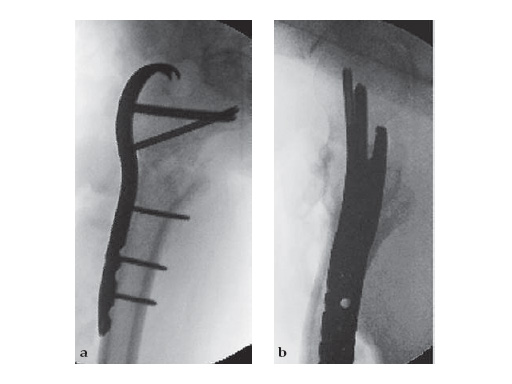

83-year-old maletrapped under tree he had cut downIDDM, HTN, CAD, etcJehovahs witnesson Plavix

Case provided by Keith Mayo, Tacoma, USA